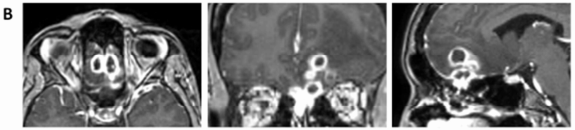

1个月后,MRI提示病灶体积略有缩小(图1C),我太开心了。由于病灶迅速缩小,所以我准备再等等。

图1C

然而,5个月后再次复查MRI,发现肿瘤体积再次显著增大,病变已累及筛窦及额叶实质(图1D)。

图1D:第二次活检后5个月,病灶再次增大